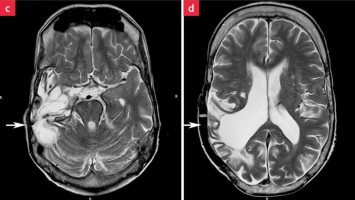

Normaler Verlauf nach Hirntumor?

Der Fall eines 52-jährigen Mannes verdeutlicht, warum es sinnvoll ist, Diagnosen zu hinterfragen. Er kam mit seinem Betreuer zur Kontrolle nach einem Anfallsrezidiv. Anamnestisch lag ein Astrozytom vor, das bereits mehrfach operiert wurde. Auffällig waren seine Schwerhörigkeit und sein unsicherer Gang.

Kutane Arzneimittelreaktion/© Hötzenecker, W., Heimlich-Manöver/© Widmer, N; Heimes, D / all rights reserved Springer Medizin Verlag GmbH, Aufbau bei einer endoskopische Mittelohrchirurgie/© Mir-Salim P., Berlin, Wespen auf Stein/© merlion / Getty Images / iStock (Symbolbild), Schilddrüse einer Patientin wird untersucht/© Werner / stock.adobe.com (Symbolbild mit Fotmodellen), Volumetrie des Bulbus olfactorius/© Keweloh S.. et al. doi.org/10.1007/s00106-025-01650-z unter CC-BY 4.0, Augen und Nase einer Frau/© AlexanderFord / Getty Images / iStock (Symbolbild mit Fotomodell), Eine ältere Frau schaut in die Ferne/© RgStudio / Getty Images / iStock (Symbolbild mit Fotomodell), Transnasales Ösophagoskop/© F. Michel, Seeheim-Jugenheim, Ex vivo konfokales Laserscanmikroskopiebild eines Morbus Bowen/© Grunewald S et al. / all rights reserved Springer Medizin Verlag GmbH, Einweckglas mit Hering/© FoodieMedia / Getty Images / iStock (Symbolbild), Zwei Injektionspens mit Semaglutid/© Kassandra / Stock.adobe.com, Gewitter mit Blitzschlag/© solarseven / Getty images / iStock, Ulzerative Form des oralen Lichen planus/© Abdusalamov K. et al. doi.org/10.1007/s00105-025-05540-x unter CC-BY 4.0, Otitis externa/© Dr. P. Marazzi / Science Photo Library (Symbolbild), VMAT-Bestrahlungsplan einer definitiven Radiochemotherapie eines linksseitigen, lokal fortgeschrittenen Tonsillenkarzinoms/© Schnellhardt, S et al. / all rights reserved Springer Medizin Verlag GmbH, Frau hustet/© Suzi Media Production / Getty Images / iStock (Symbolbild mit Fotomodell), Tympanometrie bei einer Frau/© Viacheslav Yakobchuk (Symbolbild mit Fotomodell), Stimmlippeninjektion in der HNO-Praxis/© Markus Hess, Mann erhält eine Spritze im Gesicht/© Alvaro / Stock.adobe.com (Symbolbild mit Fotomodell), Ein Arzt sprüht ein antimikrobielles und entzündungshemmendes Spray in den entzündeten Hals eines Mädchens./© HENADZY / Stock.adobe.com (Symbolbild mit Fotomodell), Junger Mensch bekommt Spritze verabreicht/© mapo / Getty Images / iStock (Symbolbild mit Fotomodellen), Bestrahlungsplans einer Wirbelsäulenmetastase eines oligometastasierten Prostatakarzinoms/© Springer Medizin Verlag GmbH, Cholesterolgranulom im MRT/© Frederik F/ all rights reserved Springer Medizin Verlag GmbH, Schimmelbefall an der Wand/© Bigy / Stock.adobe.com (Symbolbild), Rasterelektronenmikroskopische Aufnahme von Nanopartikeln/© Hansen S. et al. doi.org/10.1007/s00106-025-01633-0 unter CC-BY 4.0, Medulläres Schilddrüsenkarzinom linker Schilddrüsenlappen in der Sonographie/© Lorenz K et al. / all rights reserved Springer Medizin Verlag GmbH, Sonnenhüte (Echinacea)/© Wieland Teixeira / Getty Images / iStock (Symbolbild mit Fotomodell), Körperstereotaxie einer Lebermetastase im Segment VIII am MR-LINAC/© Ehret, F. et al. / all rights reserved Springer Medizin Verlag GmbH, Eine ältere Frau riecht an einem Basilikumblatt/© Halfpoint / Stock.adobe.com (Symbolbild mit Fotomodell), Mann hustet/© kostyha / stock.adobe.com (Symbolbild mit Fotomodell), Titel/© J. Hornung, Erlangen, Senior hält sich vor Schmerzen an den Hals/© brizmaker / Getty Images / iStock (Symbolbild mit Fotomodell), Chor von älteren Menschen/© Highwaystarz-Photography / Getty (Symbolbild mit Fotomodellen), Eine junge Frau spült sich mir einer Nasenspülung die Nase/© puhhha / Getty Images / iStock (Symbolbild mit Fotomodell), Kleiner Junge mit Pille auf der Zunge/© redpepper82 / stock.adobe.com (Symbolbild mit Fotomodell), Frau mit Kopfschmerzen/© MaximFesenko / Getty Images / iStock (Symbolbild mit Fotomodell), Normaler Verlauf nach Hirntumor?/© Wolfgang Freund, Szintigraphie der Schilddrüse mit zwei Knoten/© AniphaeS / Getty Images / iStock, Patient mit Bauchschmerzen beim Arzt/© anon / Stock.adobe.com (Ausschnitt; Symbolbild mit Fotomodellen), Mann erleidet Schwindel/© Tunatura / Getty Images / iStock (Symbolbild mit Fotomodell), Ärztin untersucht ältere Frau/© peopleimages.com / stock.adobe.com (Symbolbild mit Fotomodellen), Infusion/© georgeoprea9 / Getty Images / iStock, Frau wird Blut abgenommen/© andresr / Getty Images / iStock (Symbolbild mit Fotomodellen), Junge Ärztin vor einem Triage-Zelt/© Milos / Stock.adobe.com (Symbolbild mit Fotomodell)